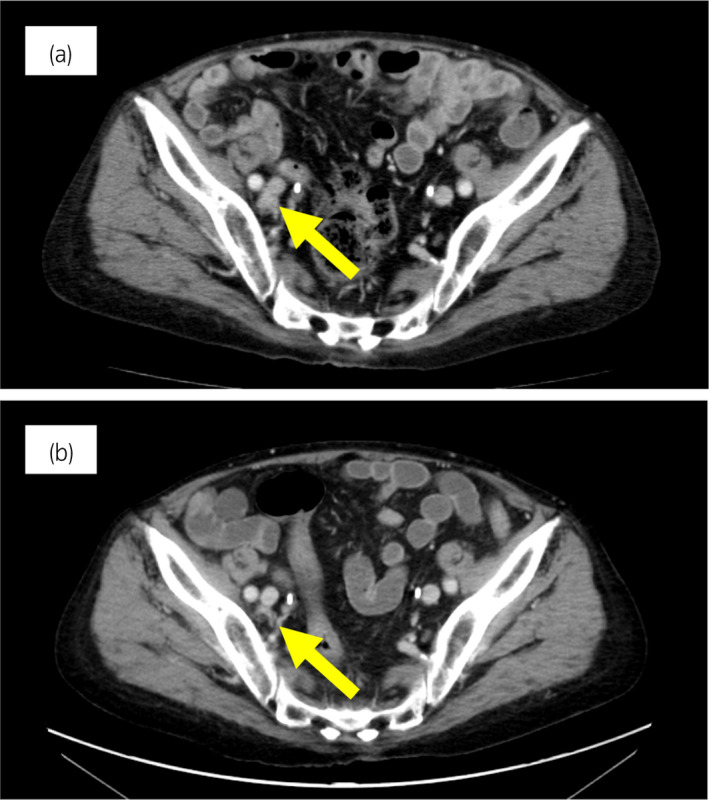

70 歲男性被診斷為轉(zhuǎn)移性 PC,cT3bN1M1b,Gleason 評分(GS)為 4 + 5 = 9,前列腺特異性抗原(PSA)水平為 40.8ng/ml,3 年前伴有胸椎轉(zhuǎn)移。 對前列腺進(jìn)行聯(lián)合雄激素阻斷 (CAB) 治療和質(zhì)子放射治療 (78.0Gy/39fr)。 PSA 水平降至 <0.01ng/ml,CAB 在 2.5 年后停止。 停止 CAB 五個(gè)月后,他出現(xiàn)背痛,PSA <0.01 ng/ml。 計(jì)算機(jī)斷層掃描 (CT) 掃描檢測到多處肝、骨和淋巴結(jié)轉(zhuǎn)移,神經(jīng)元特異性烯醇化酶 (NSE) 水平高達(dá) 171ng/ml(圖 1a)。 骨轉(zhuǎn)移活檢顯示神經(jīng)內(nèi)分泌前列腺癌 (NEPC) 的診斷(圖 2),患者被轉(zhuǎn)診至佳學(xué)基因合作醫(yī)院。 內(nèi)分泌腫瘤正確治療醫(yī)生用順鉑、依托泊苷和亮丙瑞林治療。 第三個(gè)療程后,轉(zhuǎn)移部位明顯縮?。▓D 1b)。 順鉑和依托泊苷治療 1 年,但患者因神經(jīng)病變要求停藥。 他開始服用恩雜魯胺。 治療 3 個(gè)月后,患者出現(xiàn)背痛和左鎖骨下淋巴結(jié)腫大(圖 3a)。 肝轉(zhuǎn)移保持不變,順鉑治療后縮小。 通過腫瘤正確用藥850基因檢測證實(shí)了 BRCA2 突變。根據(jù)基因檢測結(jié)果,主治腫瘤科醫(yī)生給予了奧拉帕尼。 三個(gè)月后,背痛好轉(zhuǎn),淋巴結(jié)轉(zhuǎn)移縮小,確定為部分緩解(PR)(圖3b)。 肝轉(zhuǎn)移灶保持不變。

圖1:病例1.順鉑和依托泊苷三個(gè)療程前后的腹部CT圖像。 (a) 治療前和 (b) 治療后。